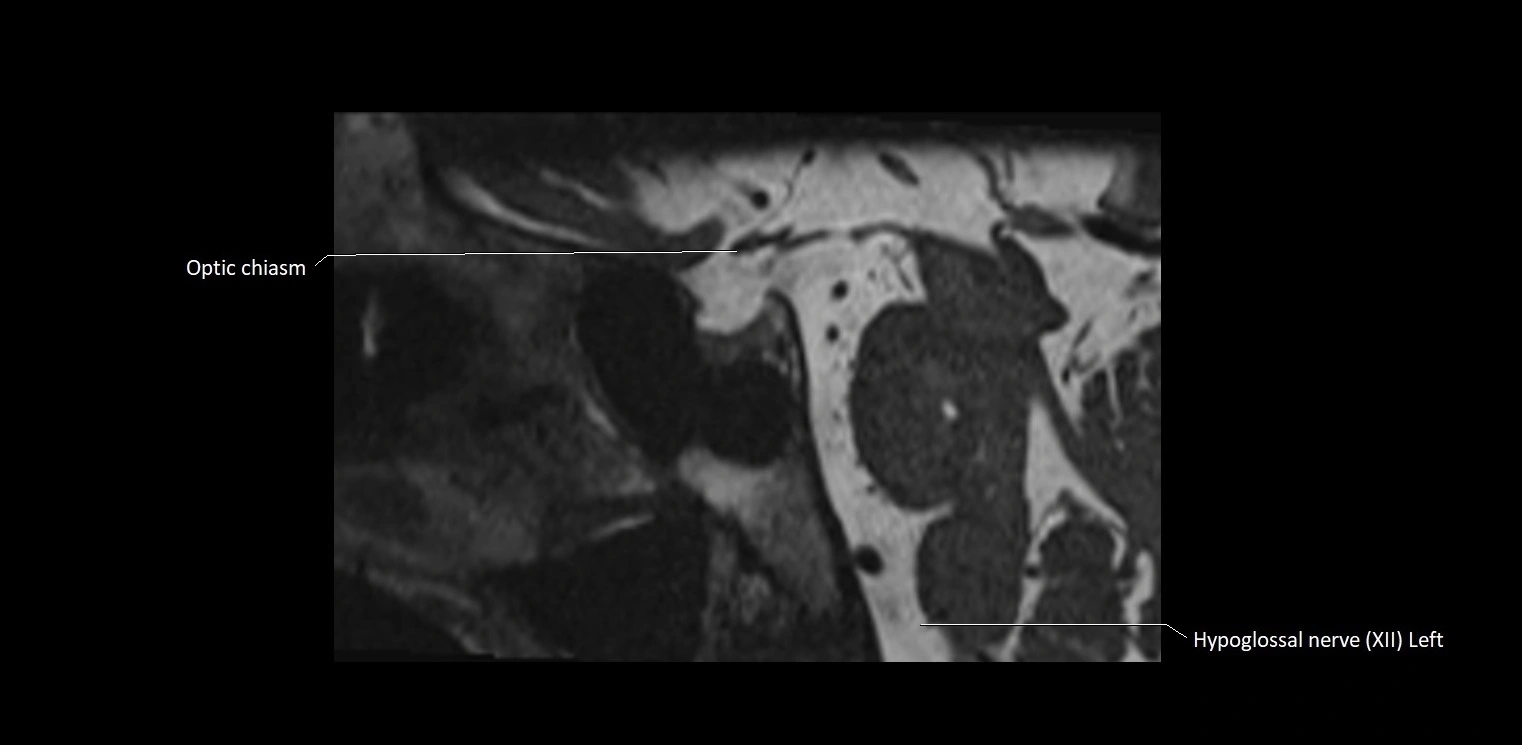

MRI images

image